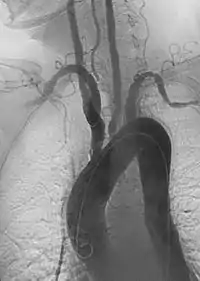

Imagen angiográfica oblicua anterior izquierda de la arteritis de Takayasu que muestra áreas de estenosis en múltiples grandes vasos | ||